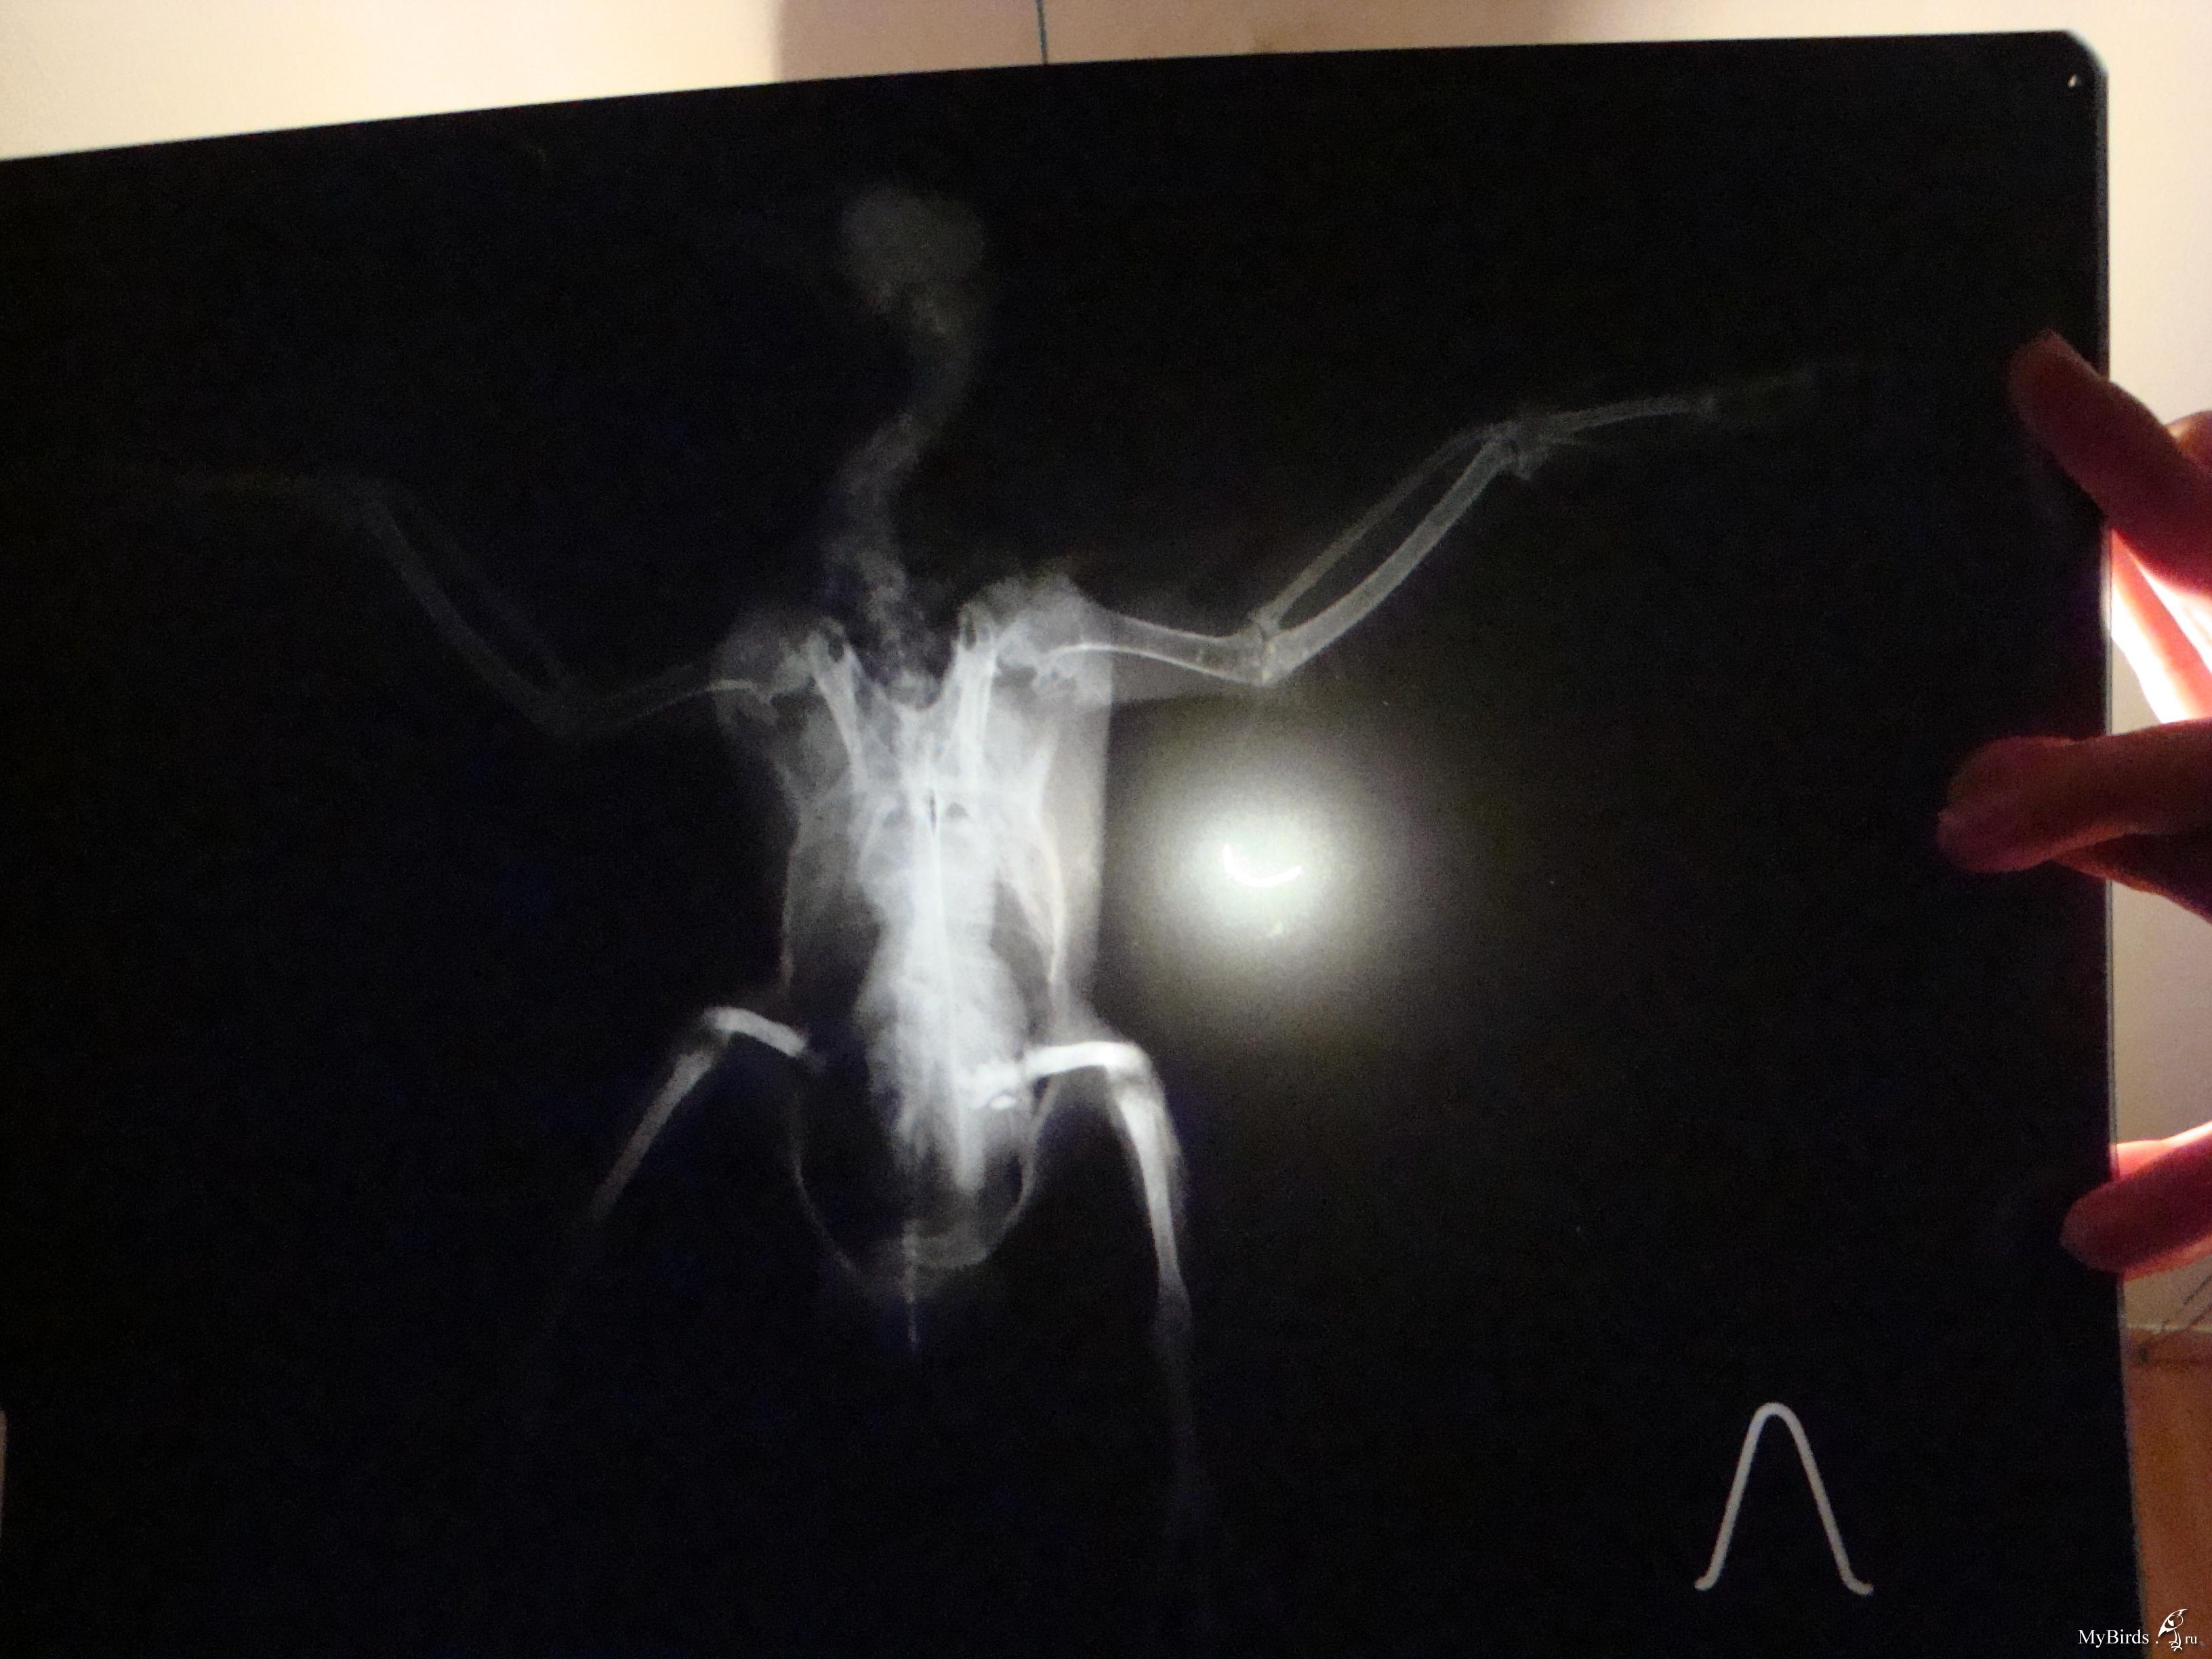

галина владимировна Опубликовано 11 сентября, 2009 Автор #118 Опубликовано 11 сентября, 2009 Это снимки Серого(тот,что с крылом).Хирург осмотрел крылья,проверил на рентгене и сказал,что перелома нет.У меня просьба.Пропишите пошагово ЧТО ДАВАТЬ,СКОЛЬКО И КАК ДОЛГО.Начиная с пробиотиков.И,если нужны витамины,то какие и тоже сколь.Схему лечения пропишите,пожалуйста,подробно(как для особо одаренных). Теперь Лапушка(тот,что с лапами).Для него такая же подробная нужна схема лечения.И чем протирать его гузку(попку).А то он лежит в своем помете часами. .Снимки,конечно ,оставляют желать лучшего.Но ,когда они были мокрыми,было видно хорошо.А высохли и изображение исчезло. У гули перелом обеих конечностей и перелом правого крыла.Хирург сказал,что крыло заживет само.А вот лапы..Переломы старые.Одна лапка сломана близко к суставу.Ее никто лечить не будет.А другую можно восстановить.Нужна операция. Операция стоит 6 тысяч.Помогите,пожалуйста, собрать средства!

Cheshirski Опубликовано 12 сентября, 2009 #120 Опубликовано 12 сентября, 2009 галина владимировна, поправил ваш пост с фотографиями - для удобства. Остальное - сейчас посмотрю-подумаю, и напишу. Снимки,конечно ,оставляют желать лучшего.Но ,когда они были мокрыми,было видно хорошо.А высохли и изображение исчезло.676983[/snapback] Маленький совет - просто вдруг в будущем пригодится. Снимки фотографировать лучше либо прямо на негаскопе (приспособление с подсветкой у врача в кабинете), либо на чем-то подобном дома (вроде светильника с лампами дневного света и молочным стеклом), а на худой конец - просто на окне, приклеив к стеклу скотчемза уголки, днем на фоне неба.Но ничего, и так все достаточно видно. Серенький. Да, переломов нет. Не видно и артроза - последствия сальмонеллы, к примеру - суставчики чистые (просто есть возможность сравнить - у меня есть снимок моего сальмонеллезника с артрозом). Тогда подвисание крыла - следствие ушиба или небольшого растяжения - они на снимке могут быть и не видны (сильные - видны в виде затемнения - притока крови к пострадавшему месту).Он не истощен? Пока кормите и добавьте в воду Ветом 1.1 - он есть? А в клюв ампульный препарат траумель, по такой схеме:Первый день приема - 2 капли в клюв каждые час.Второй день - 2 капли в клюв каждые 2 часаТретий день - 2 капли каждые 3 часа, и далее даете так, чтобы в день было не менее 3-4 приемов. Можно еще и крыло мазать траумелем (мазь), но если перьев много - то не стоит - оперение замаслится.И посмотрим за состоянием. Лапушка. Перелом крыла - да, такой сам срастется, если крыльями очень махать не будет. Смещение есть, но небольшое, на локтевой кости около запястного сустава. Даже летать сможет, скорее всего. И не исключено, что прилично летать.Лапы.Правая - да, трудный перелом. Думаю, стоит все же зафиксировать его, примерно вот так:Здесь черным обозначены кости, красным - место перелома, синим - плотный материал, вроде плотного картона, вырезан по месту, его два куска - с обоих сторон лапы - снаружи и изнутри, между лапой и телом. Конечно, подсогнуть надо будет, чтоб лапку облегал. А зеленым - места фиксации этой шины лейкопластырем. Другой вариант - выгнуть нечто подобное из жесткой (стальной) проволоки, и тоже закрепить на лапе пластырем. Возможно, что-то и удастся сделать, чтоб лапа более или менее правильно срослась. Левая. Тут попроще, кость сломана почти в середине. Что за операцйия предполагается? Остеосинтез - то есть, установка спицы? Попробуйте с врачом поговорить - не удастся ли просто совместить перелом и тоже наложить шину? Дело в том, что остеосинтез не всегда успешен у птиц - от многого зависит, и в любом случае, надо будет обеспечить неподвижность лапы, а со спицей это не всегда удается. Хотя, если у врача есть уверенность в результате - то можно попробовать. Про помет и т.д. При таких травмах не исключен и ушиб внутренних органов - той же печени. Плюс голодовка.Давайте ей траумель так же, как и Серенькому, и Ветом в воду тоже - по четверти чайной ложки на 100 мл поилки. Плюс карсил - по полтаблетки раз в день - это для печени, растолочь и давать в клюв разведенный водой до состояния кашицы.На кандиду картина не похожа, в крайнем случае - на нечто бактериальное. Пока не давайте, но имейте под рукой ципрофлоксацин 250 мг таблетки, наверняка еще остались. Если вдруг состояние кого-то из гуль будет хоть немного ухудшаться - давайте ципрофлоксацин в следующем разведении:1/2 таблетки развести в 4 мл воды, давать по 0,2 мл 2 раза в день в клюв. Если начнете его, то не прерывайте курс, давайте 10 дней. Если все же сделают остеосинтез - тогда надо будет поколоть другое лекарство, да и еще кое-что добавить, тогда и напишу. По поводу финансов - киньте в личку полный адрес, переводом сколько-то переправлю. ПС. В форуме, как правило, бываю каждый день. Так что не пропущу, единственно - не всегда удается отвечать оперативно.